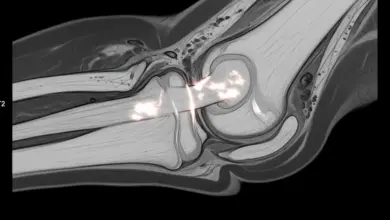

Nas radiografias feitas com o paciente em pé, costuma aparecer a calcificação típica, perto da origem femoral do ligamento colateral medial.

A ressonância magnética mostra em detalhe o LCM, possíveis áreas de edema ósseo e lesões em menisco ou cápsula, pontos importantes para definir o tratamento.